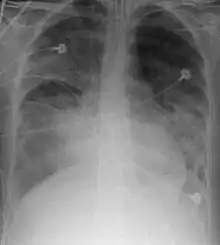

X-ray

Chest X-ray is the most common method used for diagnosis,[37] and may be used to confirm a diagnosis already made using clinical signs.[20] Consolidated areas appear white on an X-ray film.[42] Contusion is not typically restricted by the anatomical boundaries of the lobes or segments of the lung.[27][43][44] The X-ray appearance of pulmonary contusion is similar to that of aspiration,[32] and the presence of hemothorax or pneumothorax may obscure the contusion on a radiograph.[25] Signs of contusion that progress after 48 hours post-injury are likely to be actually due to aspiration, pneumonia, or ARDS.[10]

Although chest radiography is an important part of the diagnosis, it is often not sensitive enough to detect the condition early after the injury.[35] In a third of cases, pulmonary contusion is not visible on the first chest radiograph performed.[7] It takes an average of six hours for the characteristic white regions to show up on a chest X-ray, and the contusion may not become apparent for 48 hours.[7][27][43] When a pulmonary contusion is apparent in an X-ray, it suggests that the trauma to the chest was severe and that a CT scan might reveal other injuries that were missed with X-ray.[2]